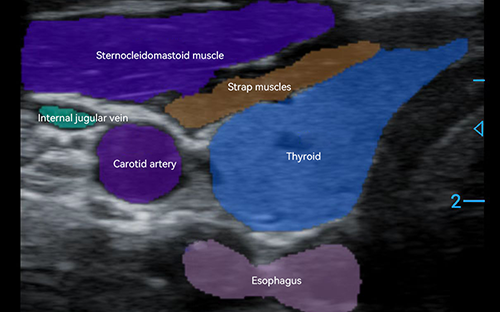

PIU1A features an advanced linear probe with high frequency and resolution that captures detailed images of superficial tissues, MSK systems, and vessels. It’s vital across scenarios: aiding pain management by visualizing soft tissue issues, supporting emergency FAST exams, and diagnosing sports injuries, such as muscle strains, for targeted treatment. Its clarity ensures clinicians to make more confident and accurate decisions.

PIU1A sets a new standard for image clarity in portable point-of-care MSK diagnostics, ensuring every detail of targeted tissues is rendered with remarkable precision—right at your fingertips. This exceptional image quality stems from its advanced spot reduction technology, engineered with Beamformer and Plane Wave Compounding algorithms that deliver consistent, high-fidelity imaging.